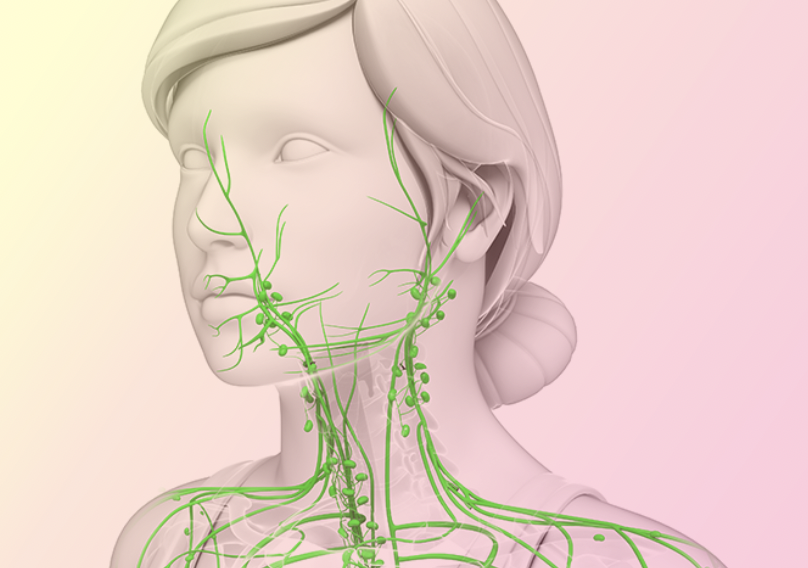

Изображения и схемы: как выглядит лимфа